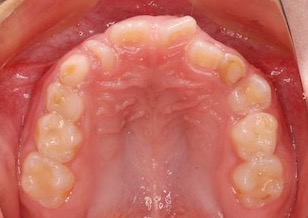

Before Ⅱ

上顎骨の劣成長に起因する骨格性反対咬合(上下顎骨の前後的な位置不正が原因)で、前歯部は反対咬合となっており咀嚼障害を認めます。 上下顎歯列において叢生(ガタガタの歯並び)と 上下顎歯列の正中線のズレが認められます。 左側上下顎第一大臼歯は交叉咬合となっています。レントゲン所見では、上顎左側犬歯が方向異常にてその隣の側切歯の歯根にぶつかって埋伏していました。